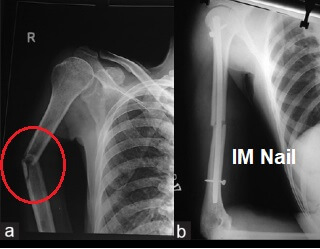

Around 10% of humeral shaft fractures will require surgical treatment. If the bone fragments are displaced, then the fragments will need to be realigned and held in place. This process is known as an Open Reduction Internal Fixation (ORIF). Usually the humerus fracture is secured with either:

In some cases a humerus fracture will treated surgically with an intramedullary rod/nail. This is when a long metal rod is placed down the middle of the bone. IM nails can be used to stabilise a humerus fracture that is between 2cm below the surgical neck and 3 cm above the elbow.

Pros: Less invasive and less chance of nerve damage.

Cons: Lower healing rate and higher rate of non-union